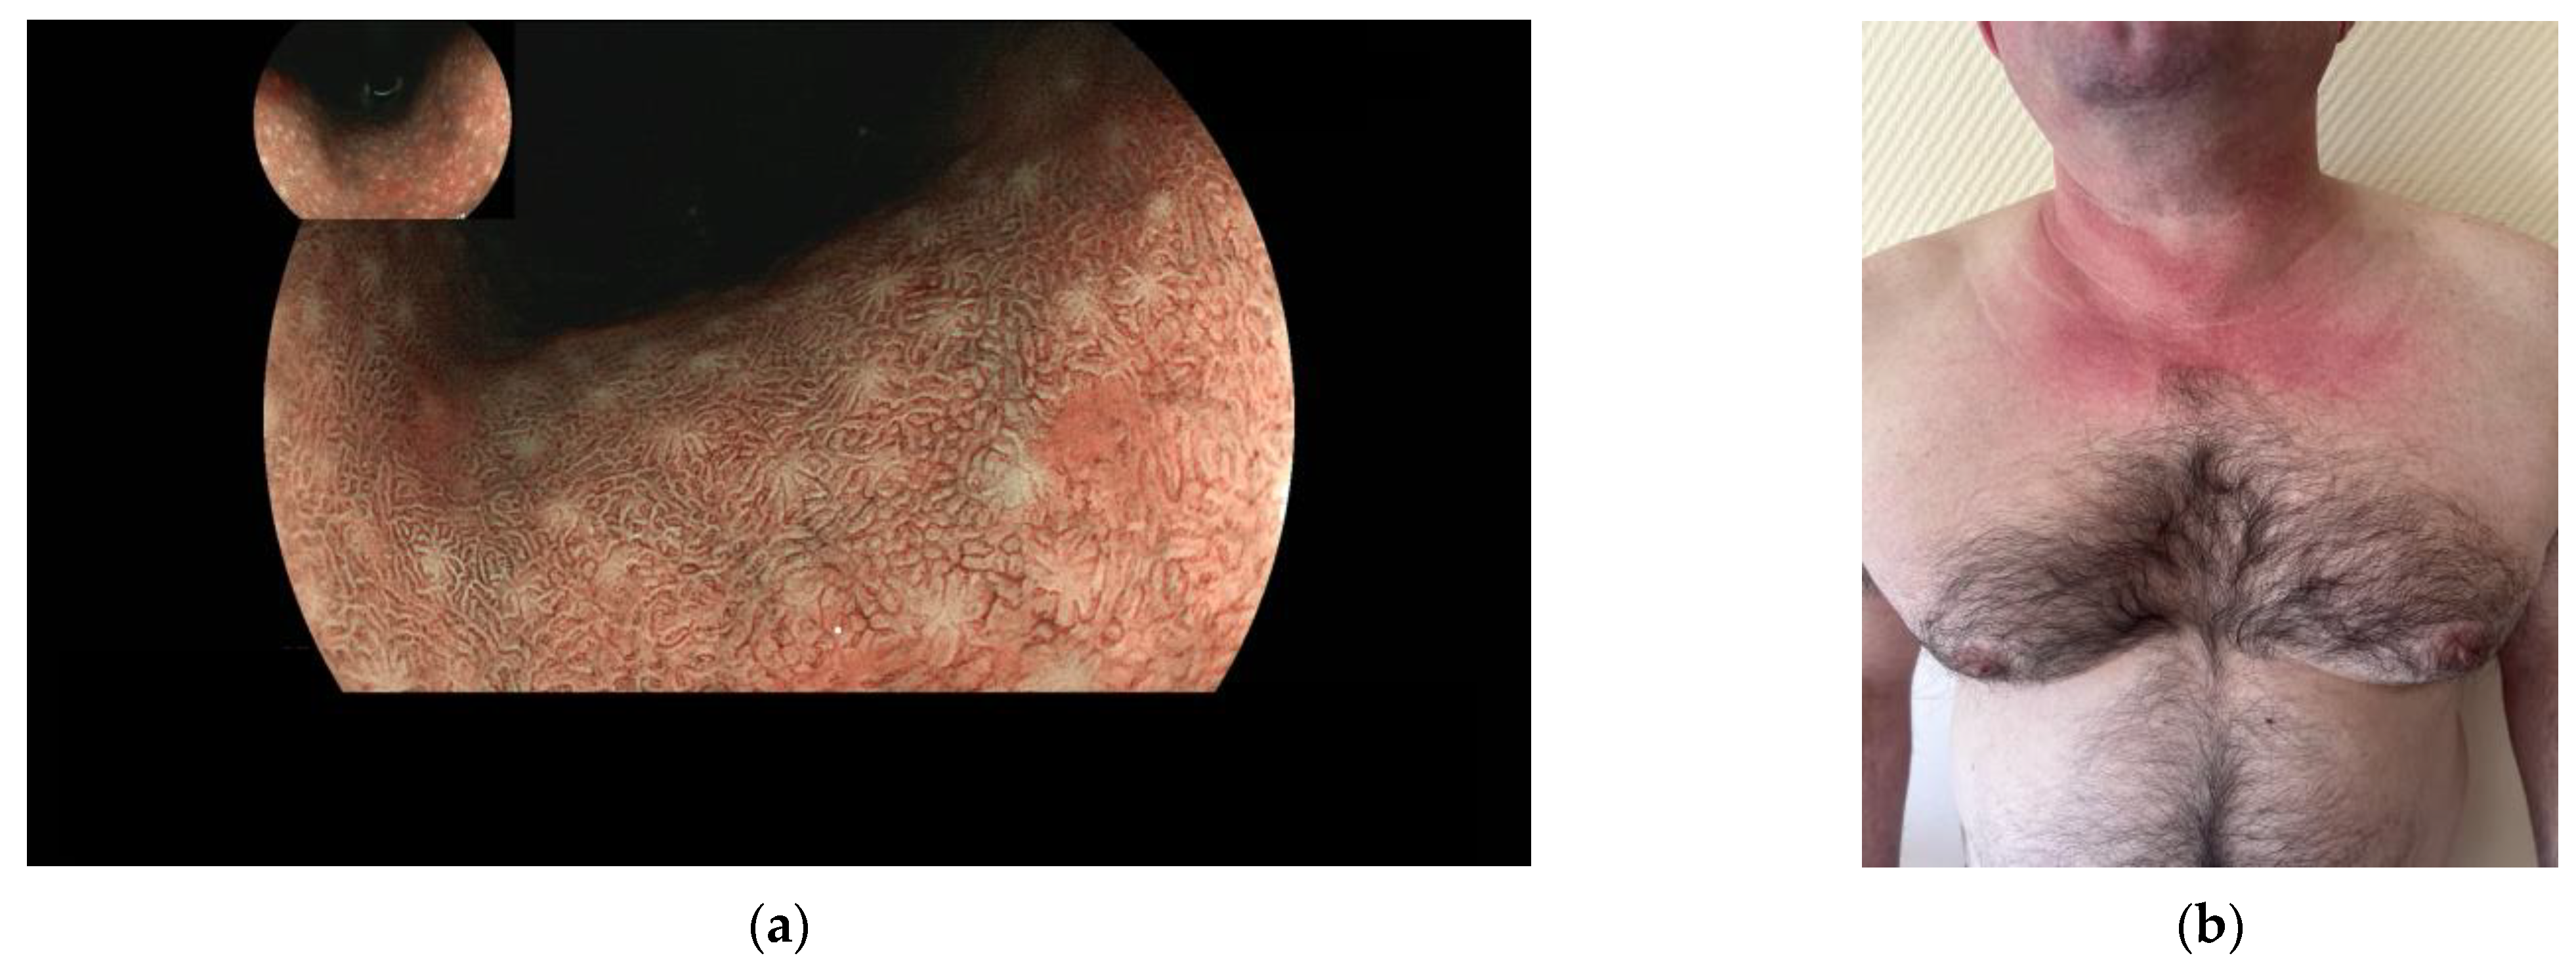

With almost one million new cases every year, gastric cancer (GC) is the fifth most frequently diagnosed cancer and the third cause of cancer-related death worldwide [1]. According to the model of gastric carcinogenesis known as “Correa’s cascade” [2], GC is preceded by the sequential development of gastric precancerous lesions (GPL) (i.e., chronic atrophic gastritis (CAG), intestinal metaplasia (IM), and dysplasia), usually following a chronic infection with Helicobacter pylori (H. pylori) [2,3,4]. Less frequently, atrophic gastritis can result from an autoimmune reaction (autoimmune gastritis, AIG), which destroys gastric glands in the fundus [5,6,7]. In H. pylori-related gastritis, the lesions first appear in the antrum and eventually spread to the corpus [5,6,8,9]; in contrast, in AIG, the lesions are typically limited to the corpus (Figure 1a).

(a) Upper gastrointestinal endoscopy with virtual chromoendoscopy (BLI) showing intestinal metaplasia and gastric atrophy in the corpus in a patient with autoimmune gastritis. Photo from the private archive of Dr. Nicolas Chapelle. (b) A 45-year-old male patient with dermatomyositis presented with a skin rash and pruritus. Clinical examination revealed macular erythema over the sun-exposed parts of the anterior neck and upper chest, known as “V-sign”, a skin manifestation of dermatomyositis. Data from the literature indicate a strong association between dermatomyositis and GC [14,15]. Patient informed consent for the photo publication was obtained.

To test whether a possible overrepresentation of autoimmunity-associated autoantibodies in patients with CAG could exist, this study aimed to analyze the prevalence of routinely assessed autoantibodies in patients with CAG as compared to control patients. We tested 19 different autoantibodies, including anti-nuclear antibodies (ANA), anti-parietal cell antibody (APCA), anti-intrinsic factor antibody (AIFA), and 16 different myositis-associated antibodies. APCA and AIFA were included as “classical” AIG-associated antibodies [14], and ANA were included because of their presence in multiple autoimmune diseases [17]. The panel of myositis antibodies was selected according to the data from the literature indicating a strong association between dermatomyositis and GC [14,15], while its possible association with GPL has yet to be studied. The clinical picture of dermatomyositis is presented in Figure 1b.